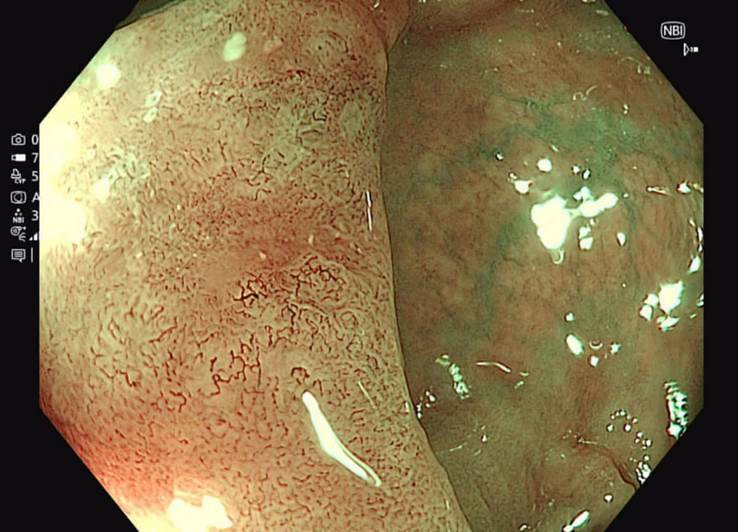

![]() |

| Hình ảnh nội soi phóng đại nhuộm màu NBI giúp tầm soát ung thư sớm. |

Phương pháp nội soi NBI còn hỗ trợ xác định ranh giới tổn thương chính xác, phục vụ hiệu quả cho các can thiệp tiếp theo như sinh thiết, cắt ESD và cắt polyp.